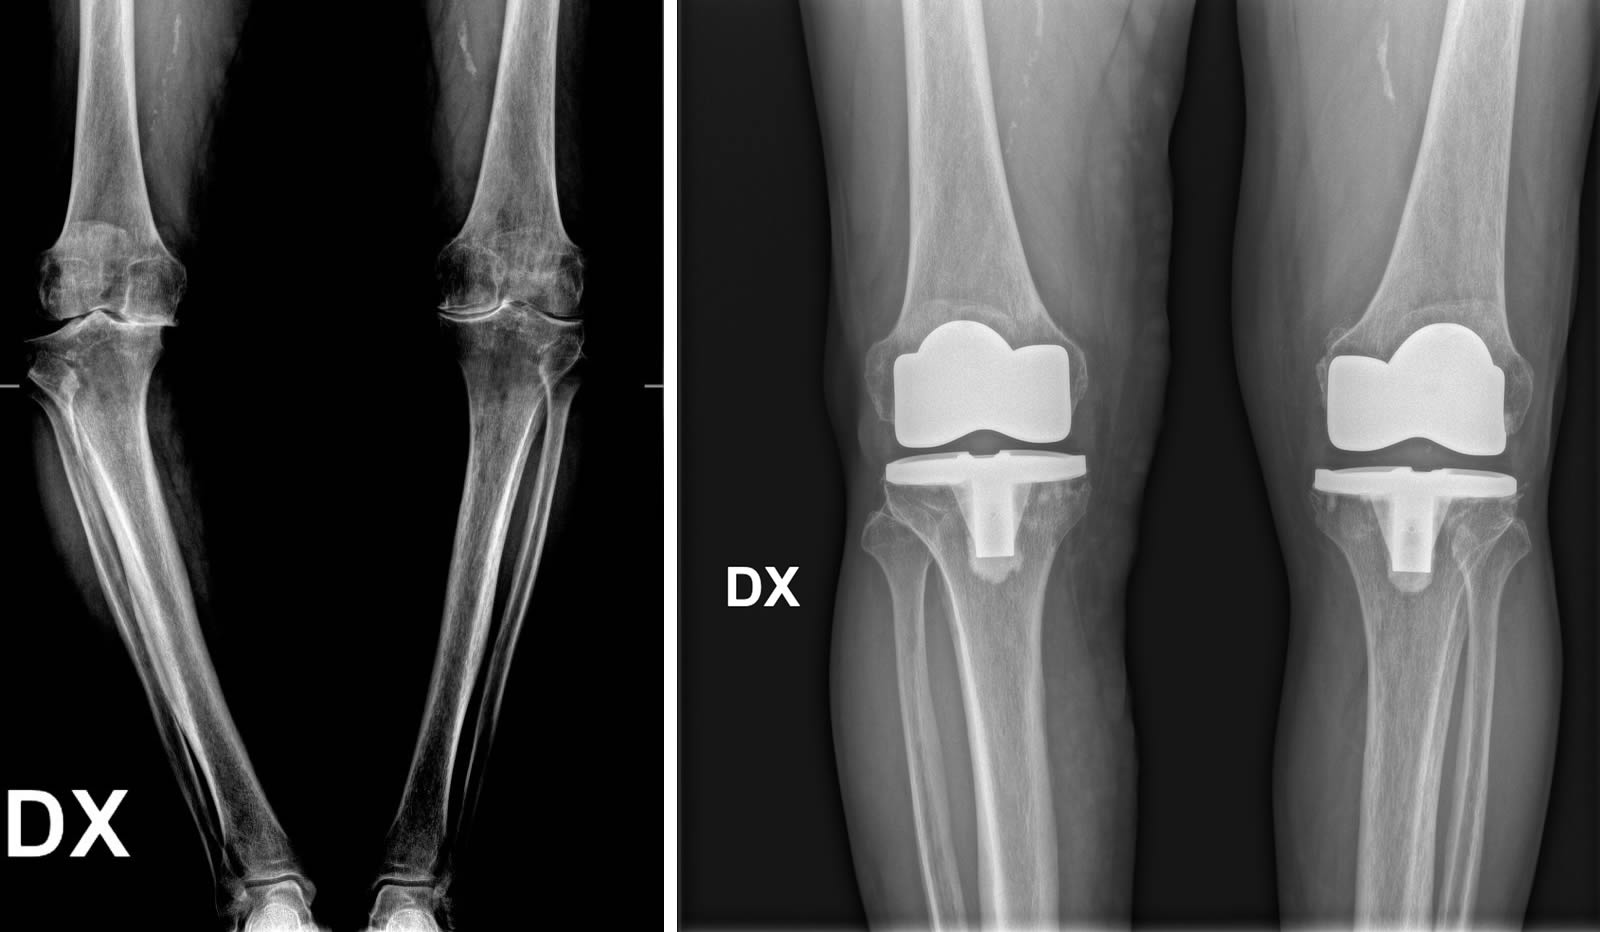

Per formulare una diagnosi corretta e ottenere un quadro clinico completo del paziente, è fondamentale eseguire una radiografia (RX) del bacino o bilaterale ginocchio in carico ovvero in piedi.

Prima e dopo l'intervento

Quando si prende in considerazione la protesi al ginocchio, si aprono diverse possibilità di intervento. È possibile optare per soluzioni mini-invasive che prevedono l'inserimento di protesi monocompartimentali, adatte a sostituire solo una parte dell'articolazione, oppure per protesi parziali o totali, in base alle esigenze e alla gravità della situazione. La scelta dell’intervento viene valutata attentamente dal chirurgo, mirando sempre a garantire il miglior recupero funzionale possibile.